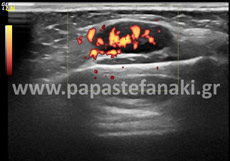

Υπερηχογράφημα Οσχέου

Στο υπερηχογράφημα οσχέου ελέγχεται η θέση, το μέγεθος και η μορφολογία των όρχεων και των επιδιδυμίδων καθώς και η αιμάτωση των αγγείων της περιοχής.

- Οσχέου

• Οσχέου